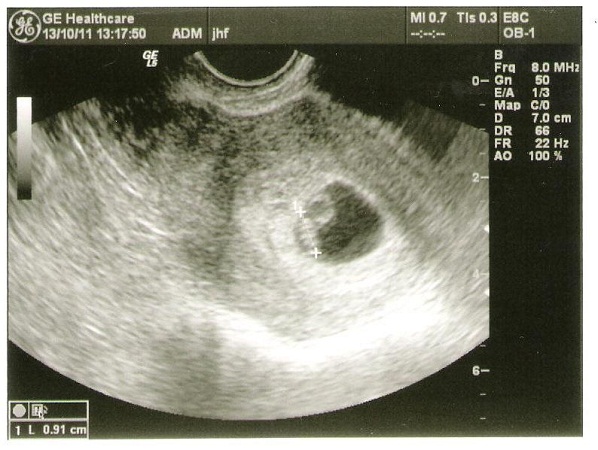

Hírek: 7 mm-es petezsák. :) Sajnos csak egy, de a férjem örül, hogy csak egy, mert 3 gyerekkel még a kocsit is le kellene cserélni. :)

17 mm-es petezsák, benne életjelenségeket mutató embrió - akinek a CRL értéke 9 mm. És dobogott a kicsi szive. Szóval Babszikával minden OK. :)

Beszkenneltem a töpörtyűt.

Sziasztok! Csoda törént, nagyon terhes vagyok :D :D :D :D :D Két gombócom van!!!!!!! 12 mm-es mindkét petezsák. Láttuk őket!!!! :lol: :lol: :lol: :lol: :lol: :lol: :lol: :lol: :lol: :lol: :lol: majd hozok képet, csak én nem tudok szekenelni

Most jövök az Uh-ról. A petezsák 20mm-es, de a kicsi csak 5 mm-es. Szépen dobogott a kicsi szíve, de a Doktornő nem biztatott sok jóval, mert ilyenkor már nagyobbnak kellene lennie. A 7 hét+4 napon volt az UH, így már tényleg nagyobbnak kellene már lennie. A jövő héten kell visszamennem, de lélekben már felkészített a műszeres befejezés valószínűségére. Persze még reménykedhetek, de ez a folyamatos bizonytalansági hinta nagyon megvisel.